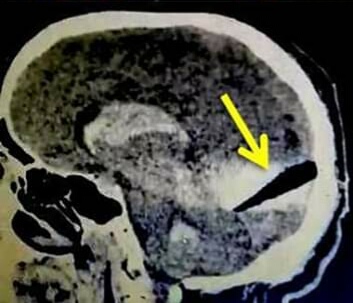

صورة توضيحية

كتب - محمد عيد: أصدر وزير القوي العاملة محمد سعفان، تعليمات فورية لمكتب التمثيل العمالي التابع للوزارة ، بالسفارة المصرية بالعاصمة الأردنية -عمان، بمتابعة إجراءات نقل جثمان المواطن المصري، عبد الجواد علي المصري عبد الرحمن الذي يعمل بالأردن ، وكذلك مستحقات لدي جهة عمله، وكان قد أصيب بطعنة سكين من مواطن أردني ، وتم إجراء عة عاجلة له كانت نسبة النجاح فيها قليلة جدا، وتوفي مساء أمس. وقال المتحدث الرسمي والمستشار الإعلامي للوزارة هيثم سعد الدين : إن المستشار العمالي بعمان أشراف الحرايري انتقل علي الفور فجر اليوم لمستشفي أربد  وتم التواصل مع أخو المتوفي للمساعدة في إنهاء الإجراءات الخاصة بشحن الجثمان وابلاغه تعازي  الوزير، كما سيتم مع المستشار اللخبر قانوني تحويل القضية من شروع في قتل الي قضية قتل وسوف يتم متابعة مستحقاته. وأوضح أن وزير القوي العاملة، كان يتابع حالة المواطن المصري بمجرد علمه بالحادث أول بأول مع المستشار العمالي ، حيث قام بزيارته بمستشفى أربد للوقوف علي حالته قبل الوفاة  وكان قد أصيب بطعنة سكين من مواطن أردني . وكشف المستشار العمالي أنه تم القبض والتحفظ على الأردني المتعدى على المواطن المصري حيث كان قد تعرض لواقعة اعتداء عليه بسكين من قبل أحد المواطنين الأردنيين، حيث وجه له طعنه في الرقبة وفي الرأس مما أدي إلي انكسار السكلخبرين داخل الرأس.